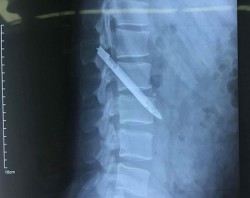

Khi bệnh nhân là một chiến sĩ công an nhập viện với triệu chứng đau ở lưng, các bác sĩ đã khám, chụp X-quang kiểm tra thì bất ngờ phát hiện lưỡi dao dài 13 cm nằm ở vùng cột sống thắt lưng suốt 11 năm.